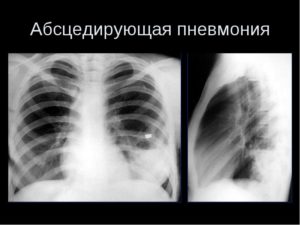

Обследование в обязательном порядке включает обзорную рентгенограмму легкого. На ранней стадии абсцедирующая пневмония схожа с другими заболеваниями дыхательной системы, и грамотно проведенная рентгенограмма позволит точно определить характер патологии. Рентгенограмма показывает, насколько распространен патологический процесс, его локализацию, возникновение дополнительных осложнений.

При затруднении в постановке точного диагноза и определении степени распространения патогенного процесса поможет компьютерная томография. Исследование позволяет четко визуализировать поражения легкого, возникшие при заболевании.